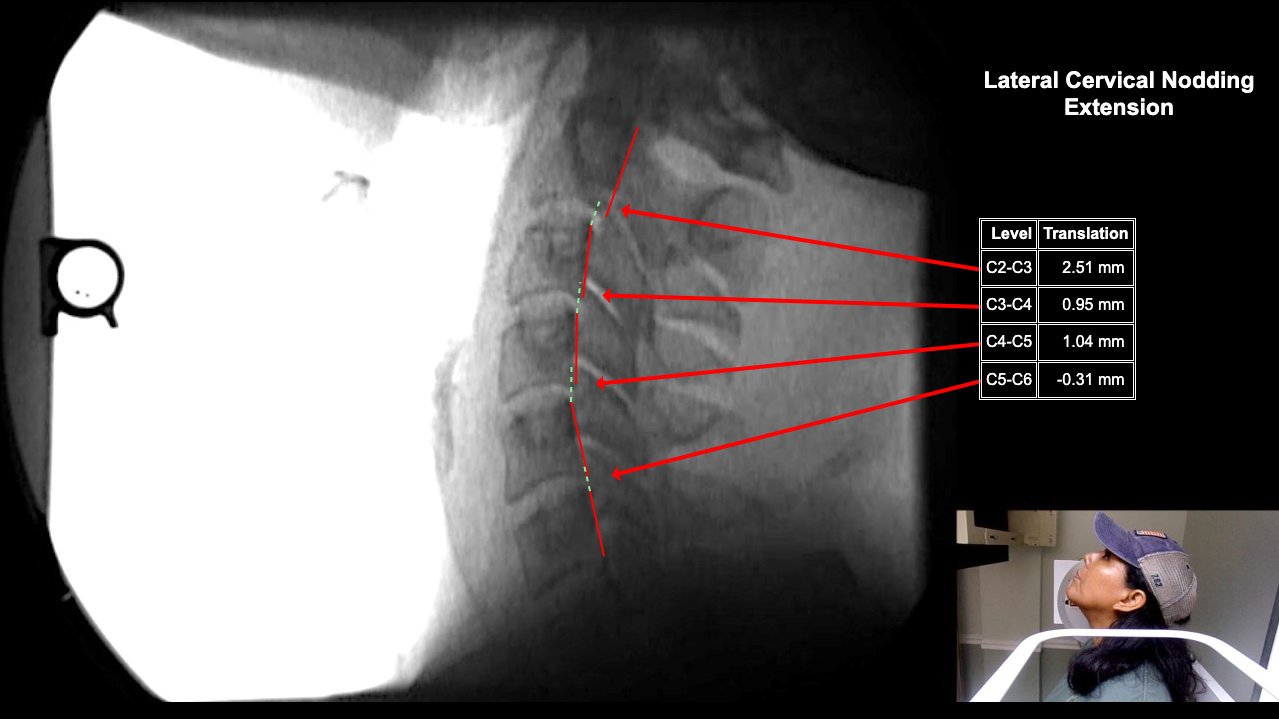

Home > Tamara Tripp 7-3-25